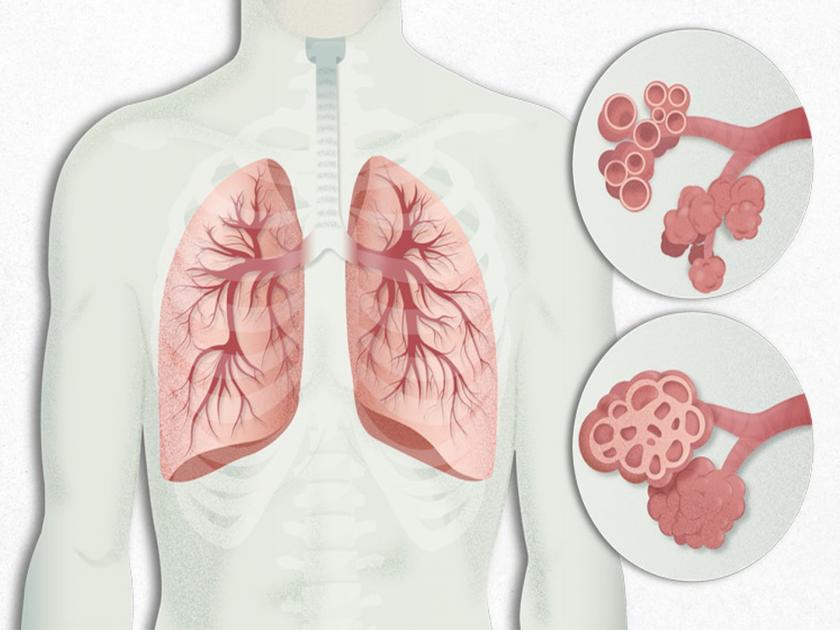

व्हेंटिलेटरचा वापर केलेले रुग्ण, रक्तदाब, डायबेटीसच्या रुग्णांसह वयाेवृद्धांना थकवा जाणवणे, दम लागणे अशी लक्षणे दिसत आहेत. काेराेना महामारीच्या विळख्यातून सहीसलामत बाहेर पडलेल्या रुग्णांना आता विविध शारीरिक समस्या जाणवत आहेत. त्यामध्ये प्रामुख्याने ज्येष्ठ नागरिक आणि रक्तदाब, डायबेटीस असणाऱ्या रुग्णांचा समावेश आहे. जिल्हा सरकारी रुग्णालयांमध्ये पाेस्ट काेविड सेंटरची व्यवस्था नसली तरी, डाॅक्टर अशा रुग्णांना माेबाइलद्वारे सल्ला देत आहेत. अशा रुग्णांनी सकस आहार घ्यावा, चांगली झाेप घ्यावी, जास्त श्रमाची कामे करू नयेत, व्यायाम करावा, फळे, भाजीपाला यांचा जेवणात समावेश करावा, अशा सूचना डाॅक्टारांकडून करण्यात येत आहेत.

ज्यांना काेराेना हाेऊन गेला आहे त्यांनी काळजी घेणे गरजेचे आहे. विशेषतः ज्यांच्या फुप्फुसांमध्ये संसर्ग झाला हाेता आणि जे रुग्ण व्हेंटिलेटलवर हाेते त्यांनी अधिक काळजी घेणे गरजेचे आहे. काेणताही आजार अंगावर काढू नये. त्रास झाल्यास तातडीने नजीकच्या रुग्णालयाशी संपर्क साधावा.

थकव्यासह दम लागण्याचा हाेताेय त्रास ज्यांना काेराेना हाेऊन गेला आहे त्यांना आता दम लागणे, थकवा येणे, झाेप न लागणे अशी लक्षणे दिसत आहेत. ज्यांना रक्तदाब, डायबेटीस यांसह अन्य आजार आहेत त्यांना याचा त्रास अधिक हाेत आहे. त्यामध्ये वयस्कर रुग्णांचा समावेश आहे. त्यामुळे चिंता वाढत आहे.